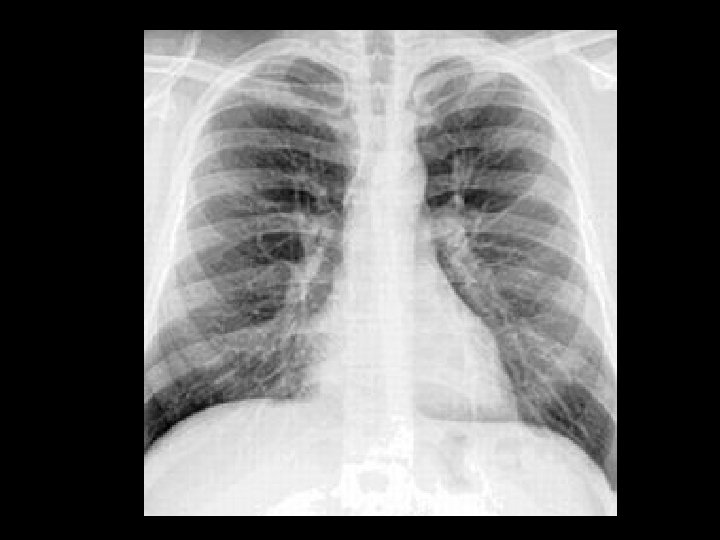

Film screen • • Radiographic Density Overall blackening of the radiographic image as a result of the energy deposited inthe film emulsion.

Film screen Radiographic Contrast / Grayscale • The difference between two adjacent • radiographic densities in the image. • • The overall number of density shades present in the image.

Image-forming x-rays • Two kinds of photons are responsible for the OD and contrast on an image: Photons that pass through without interacting and those that are scattered though Compton. • X-rays that exit the patient are remnant and those that interact with the IR are image-forming.